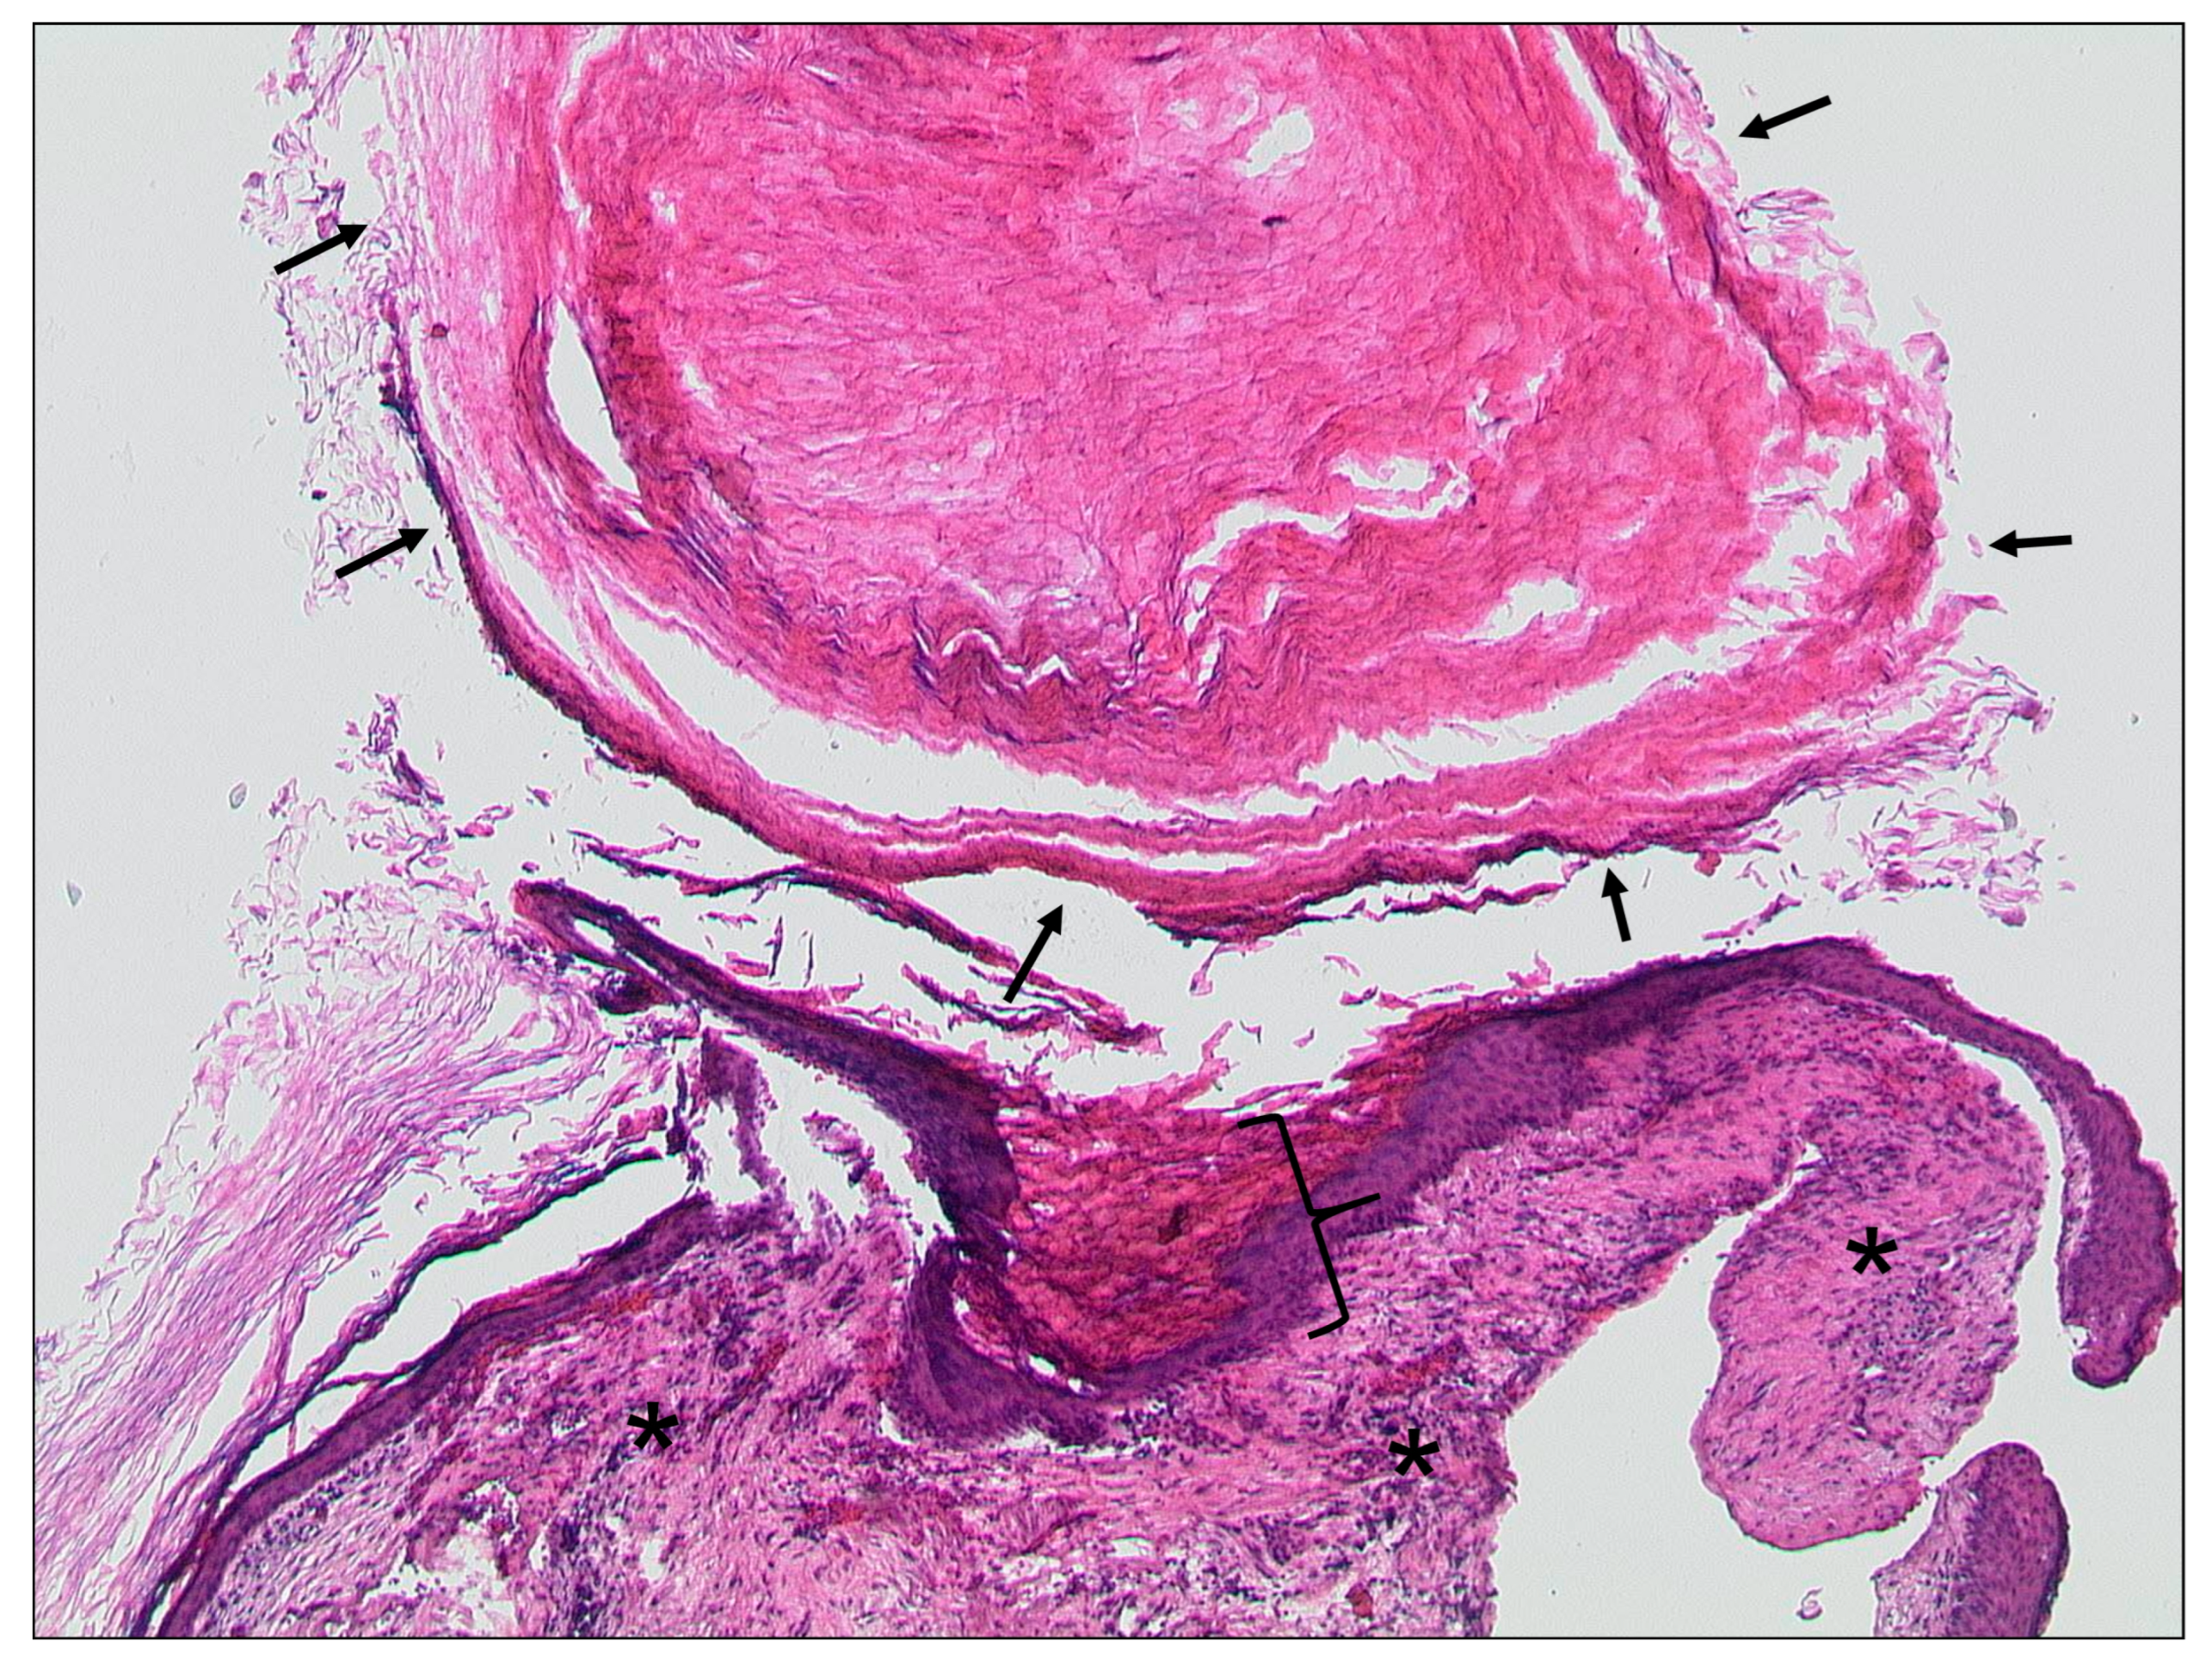

3.1.2. Cholesteatoma of the External Ear Canal

3.1.3. Auditory Canal Exostosis

3.1.4. Keratosis Obturans

3.2. Middle Ear and Mastoid